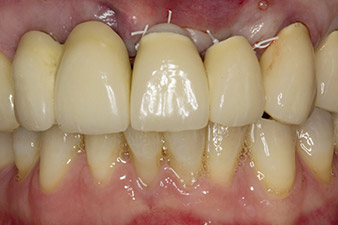

Fig. 1: The initial radiological findings revealed a splinted crown restoration requiring replacement. When the restoration was removed, teeth 21 and 22 were unintentionally extracted along with it.

When the patient first presented, teeth 21, 22 and 23 had been restored with splinted crowns, now 19 years old, which were bonded to the implants at positions 12/11 by an attachment (cf. Fig. 2).

The x-ray revealed horizontal bone loss around teeth 21 and 22 (Fig. 1). When the crown block was removed, these teeth were unintentionally extracted with it.